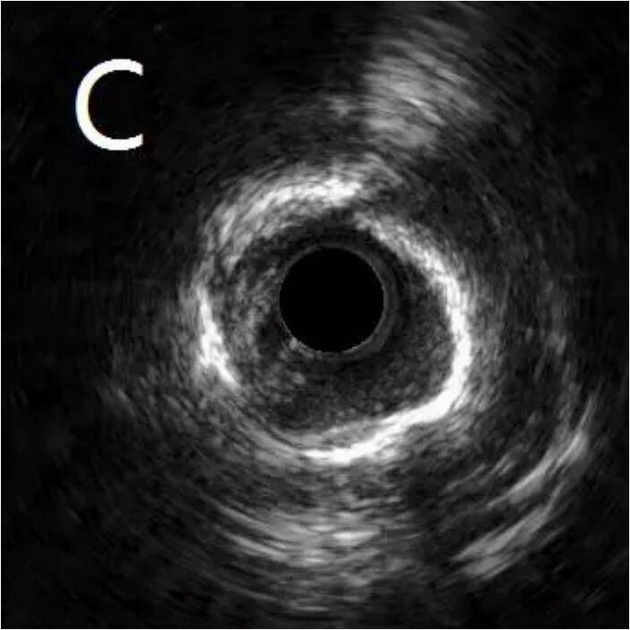

患者为77岁女性,因冠心病进行冠状动脉介入治疗,造影发现冠状动脉前降支不仅闭塞(图A),而且伴有钙化。通过不懈的努力,将闭塞的血管打开,但钙化处球囊无法将病变充分扩张(图B),意味着无法通过植入支架来维持血管管腔。于是采用血管内超声对病变处进行检测,显示病变处存在严重的360度环形钙化(图C、D)。